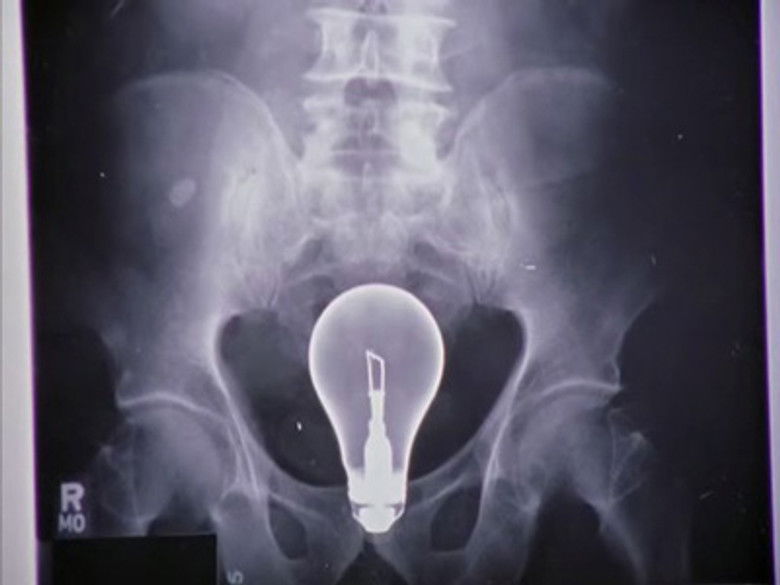

7 septembre 2004Molly travaille sur la résolution des conflits en milieu hospitalier et choisit le docteur Cox comme sujet d'étude. Pourvue de bonnes intentions, elle tente de réconcilier JD et Elliot, en compétition pour décrocher le poste de Chef des internes. Pendant ce temps, Cox, JD et le concierge essaient de résoudre le mystère de l'hôpital : comment extraire une ampoule du ventre d'un patient sans la briser ?